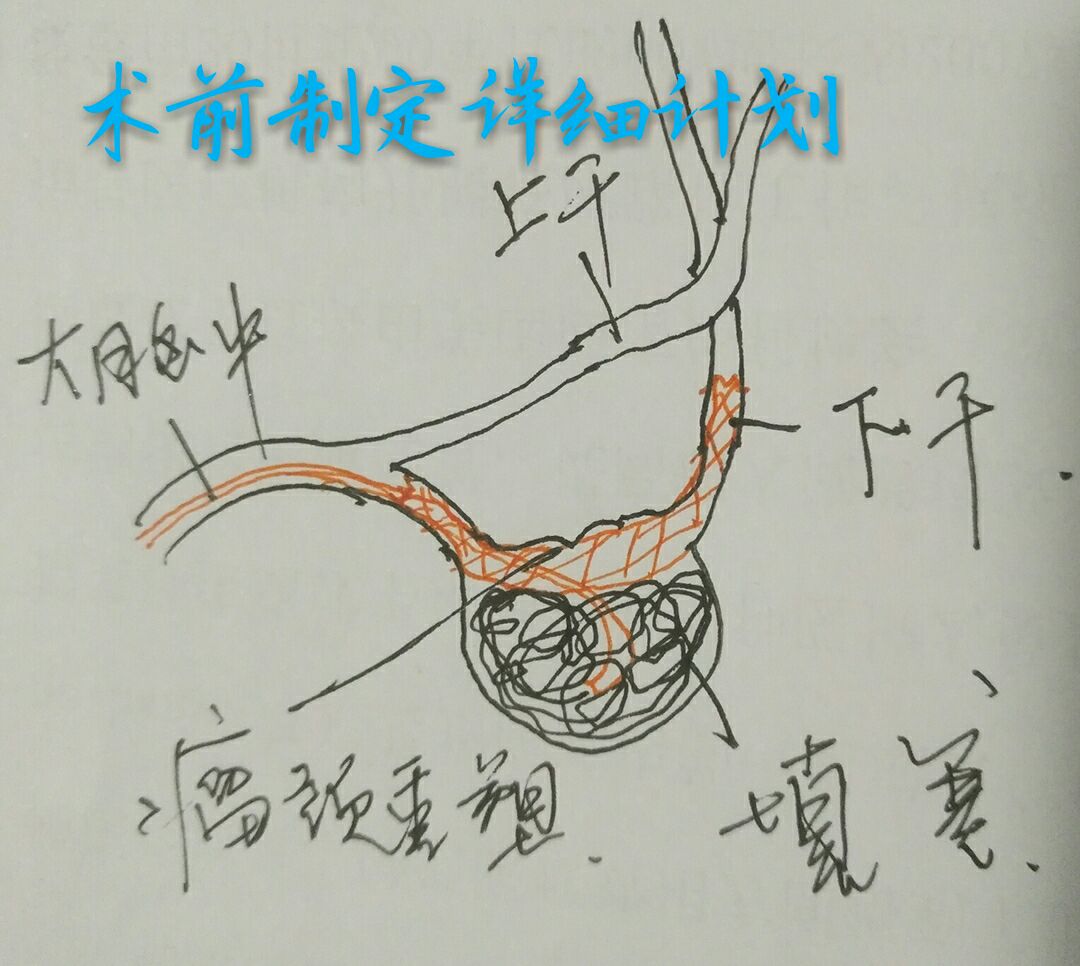

病例四:80岁男性患者,主症:头痛、脑鸣2年,DSA示左侧大脑中动脉下干大动脉瘤,绝对宽颈,载瘤动脉累及程度重

因栓塞难度大,术前做了详细、精准的计划

最准致密栓塞动脉瘤,载瘤动脉完美塑型并受到保护,难点:瘤颈极宽,辅助支架导管通过动脉瘤到达远端困难,最准微导管塑型成大弯,微导丝成袢通过动脉瘤到达远端,成功释放支架,动脉瘤栓塞后患者头痛、脑鸣症状消失